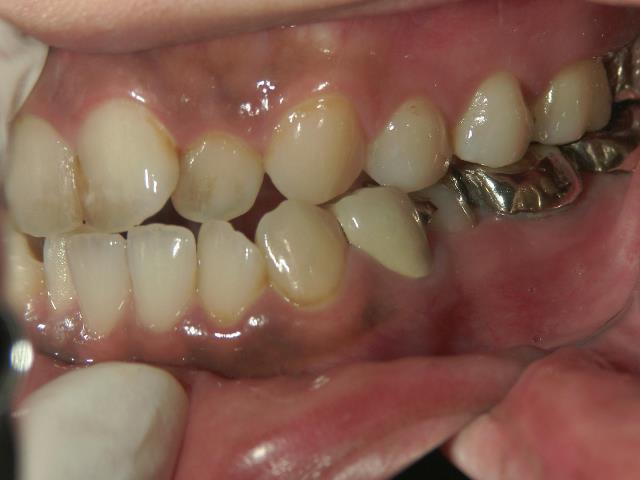

矯正歯科 治療後矯正歯科 全顎ワイヤー矯正 治療後矯正歯科(全顎ワイヤー矯正)治療後

30歳女性 浜松市北区在住

治療期間3年4ヶ月

主訴:前歯の歯並びが気になる。

矯正歯科 治療前 上顎を装置(QH)で拡大後ワイヤー矯正へ移行、右下5番左下4番 計2本抜歯叢生改善